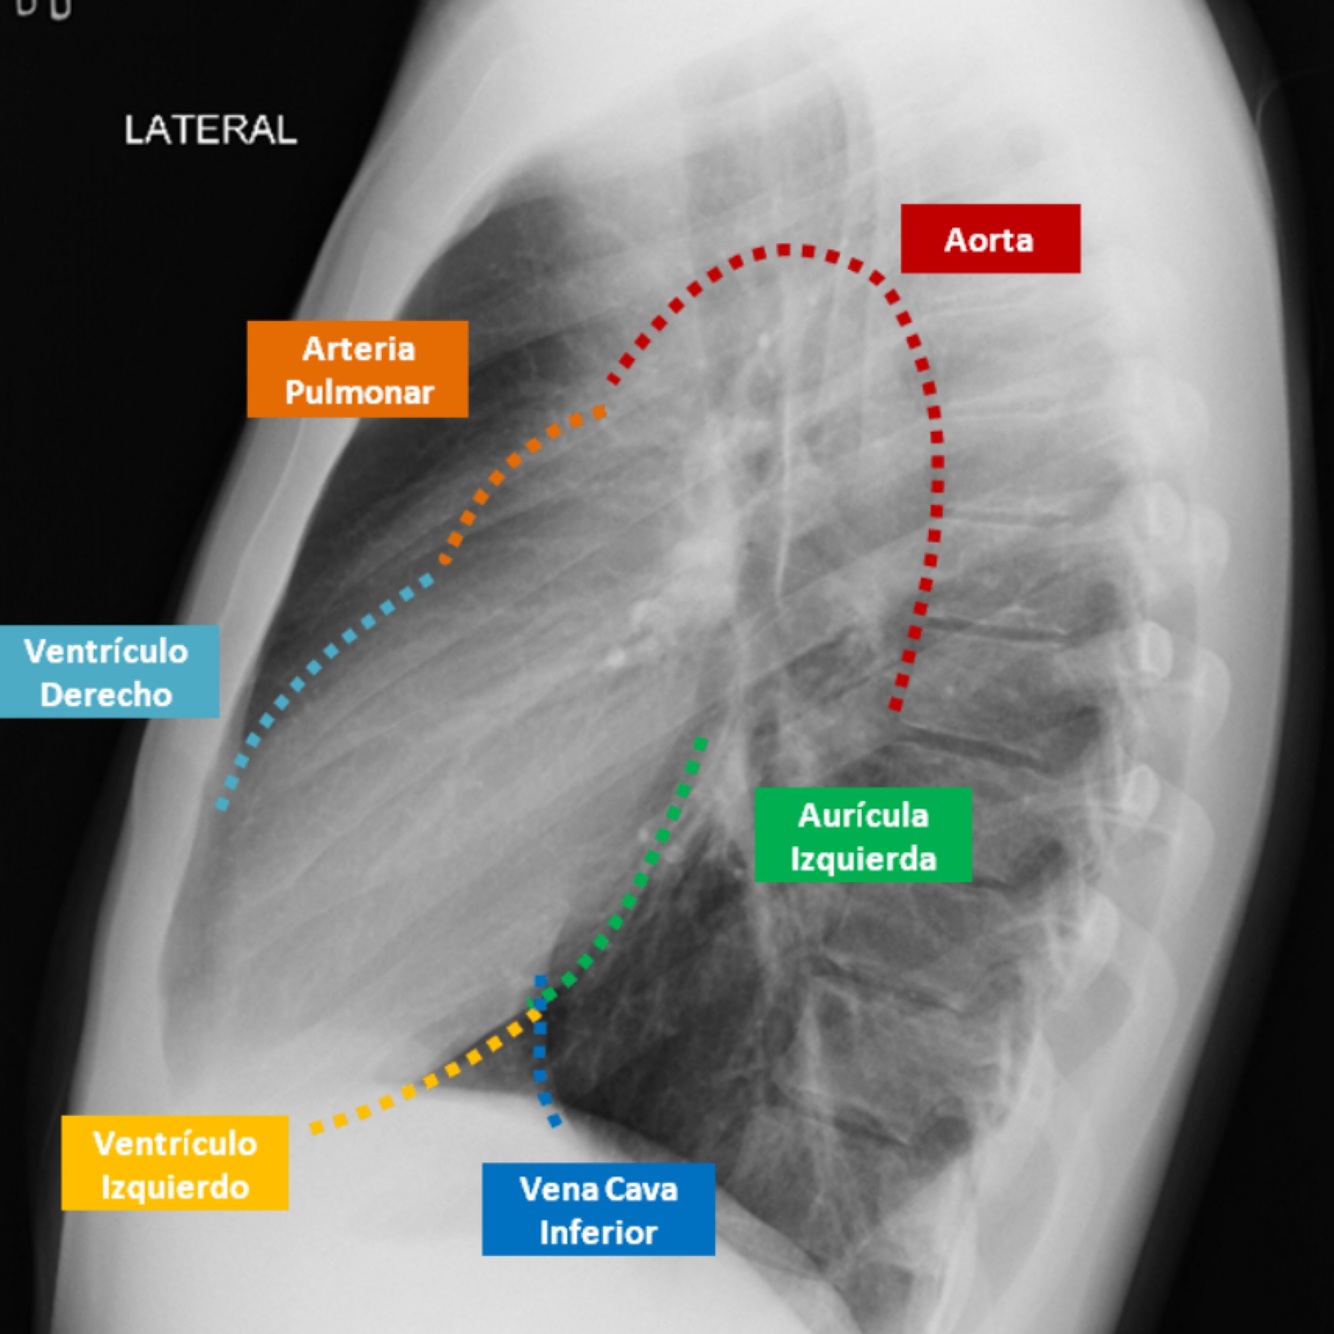

Q

Describe el perfil cardiaco